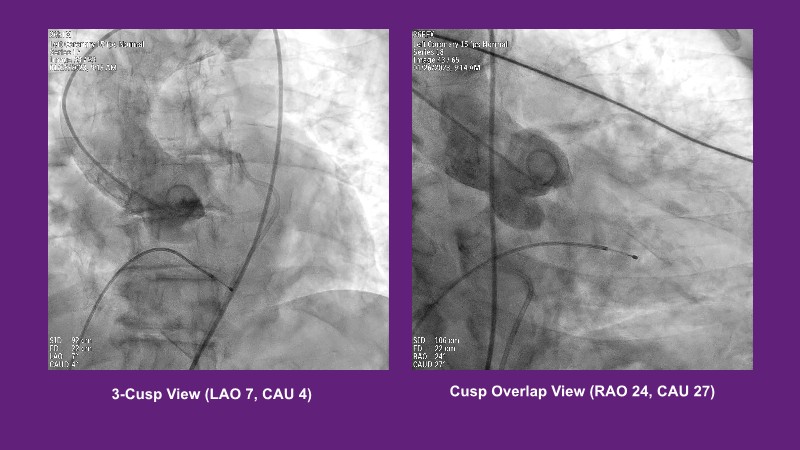

Standardised implant technique with self-expandable valve

Don’t miss this PCR Tokyo Valves 2025 session replay, where leading experts share key techniques for simplifying and optimising TAVI procedures with the Evolut device. This session covers essential insights into safely performing procedures on patients with various anatomical types using the self-expandable valve, while emphasising the importance of long-term patient care and outcomes. Discover valuable strategies for surgical explantation of transcatheter aortic bioprostheses, coronary cannulation, and commissural alignment post-TAVR. Learn expert tips for streamlining procedures, such as semi-rapid pacing, using Dryseal long, and skipping pre-BAV to improve TAVI results. Watch now to stay ahead in the field!